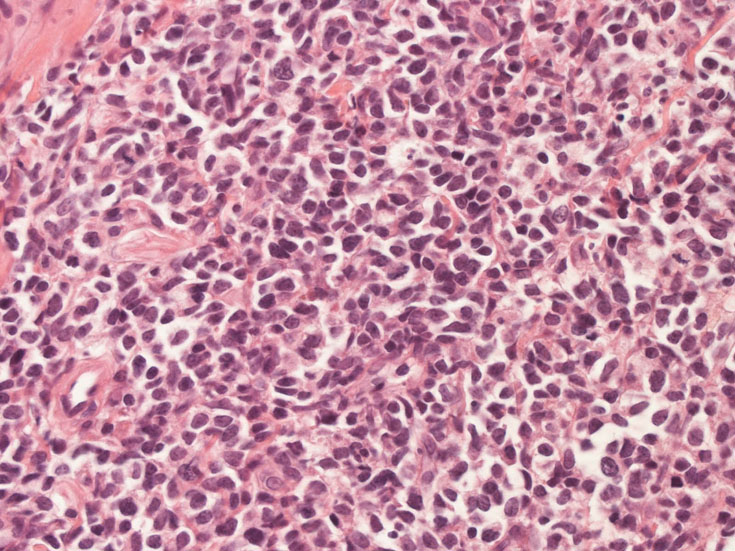

罹患リンパ節の基本構造は消失し腫瘍細胞のびまん性増殖で置換されている。非腫瘍性の小リンパ球(CD3+, CD4/8+)が濾胞様に散在して残る(Fig.01)。不整型または類円形の明るい核をもつmedium-sizeのリンパ球様細胞が密に増殖している。細胞質は乏しい(Fig.02)。CD68陽性macrophageが多く混在する部分が認められた(Fig.03)。

Fig04, Fig05は腫瘍細胞の拡大像。大型異型細胞の出現が認められる。腫瘍細胞はCD4+, CD56+, CD123+(Fig.06)